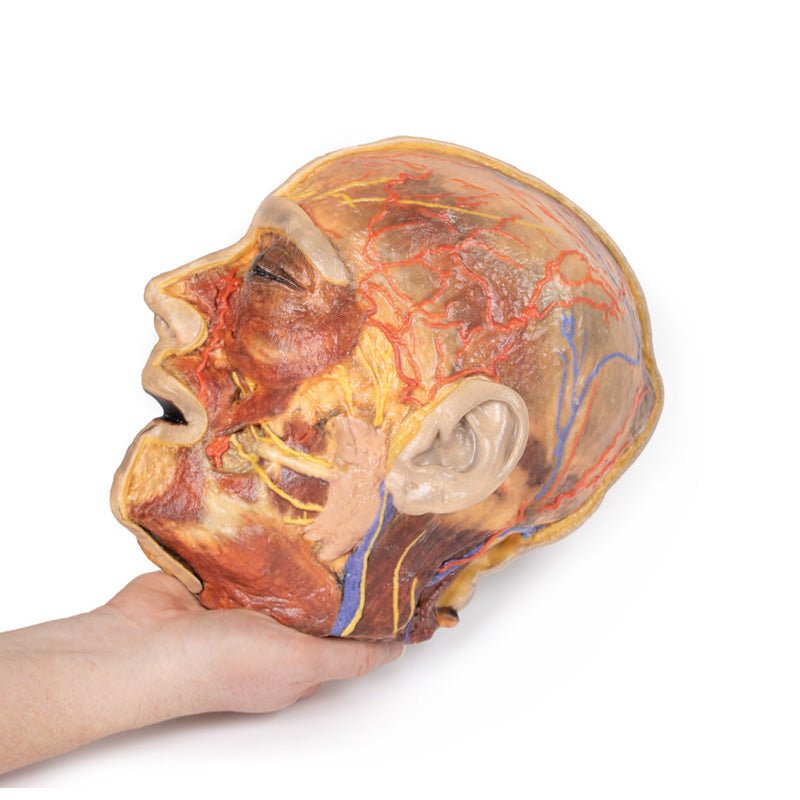

3D Printed Superficial Facial Nerves & Parotid Gland

This 3D model presents the superficial anatomy of the face and head, and compliments the superficial facial anatomy

of our HW 44 model with a more expanded dissection across the scalp and occipital regions.

The superficial

neurovascular and muscular structures in the face largely mirror the structures described in reference to our HW 44

specimen (see description), although the terminal branches of the facial nerve (CNVII) can be largely followed

across a longer course from the parotid gland and the platysma muscle has been retained superficial to the mandible

and extends towards the neck.

In contrast to the HW 44 specimen, this model has a more expansive superficial

dissection inferior to the external ear and across the posterior scalp and occipital region. This allows for an

expanded appreciation of the neurovascular distribution of the supraorbital and supratrochlear nerves and arties

with the superficial temporal artery. Inferior to the ear, the retromandibular vein has been exposed with the

ascending fibres of the great auricular nerve on its superficial surface (and further branches of this nerve on the

surface of the sternocleidomastoid muscle). At the posterior border of the sternocleidomastoid muscle the lesser

occipital nerve is just preserved, near the exiting and ascension of the occipital artery and vein near the

trapezius muscle towards the posterior scalp. Surrounding the external ear are fibres of the auricularis superior

and posterior muscles. Near the margin of the dissection window posteriorly the deep fibres of the occiptalis muscle

can be seen integrated into the epicranius (occipitofrontalis) muscle.